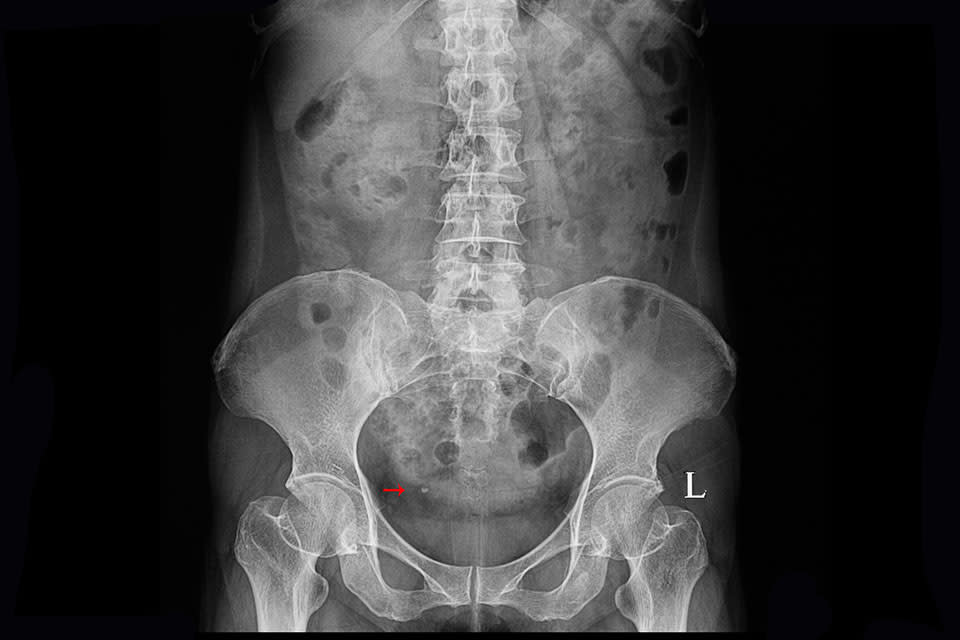

Causes urologiques : la cause principale de l’hématurie est une infection urinaire, laquelle s’accompagne de brûlures à la miction, de fréquentes envies d’uriner (pollakiurie) et de douleurs lombaires. Il peut s’agir d’une cystite (infection au niveau de la vessie), d’une pyélonéphrite (infection au niveau du rein et de l’uretère) ou encore d’une prostatite(infection au niveau de la prostate). Autres causes urologiques possibles : une tumeur du système urinaire (vessie, uretère) ou rénale, un traumatisme (lésion de la vessie, fracture du parenchyme rénal, conséquence de la pose d’un cathéter…) ou des calculs (lithiases) urinaires.

Pour diagnostiquer une hématurie, le médecin commence par échanger avec le patient (date de début des symptômes, fréquence, intensité, antécédents) puis il réalise un examen urinaire avec une bandelette pour détecter l’éventuelle présence de sang dans les urines. Il prescrit ensuite un ECBU pour préciser le diagnostic, de même qu’un examen du culot urinaire, c’est-à-dire du dépôt dû aux sédiments urinaires. Par la suite, d’autres examens vont venir éclairer la cause de l’hématurie constatée : une échographie de l’appareil urinaire (vessie, rein, uretère, urètre, prostate) ou uroscanner (examen plus précis que l’échographie dans le bilan de l’hématurie). Selon la cause identifiée, différents examens peuvent être nécessaires, comme une cystoscopie de la vessie, ou une ponction-biopsie des reins, par exemple.

Le traitement de l’hématurie dépend de la cause diagnostiquée. Ainsi, pour une cystite ou une pyélonéphrite, des antibiotiques spécifiques sont prescrits. Alors que pour des calculs urinaires par exemple, si l’expulsion spontanée n’a pas lieu, on peut envisager une fragmentation des calculs par des ondes de choc ou extraire les calculs rénaux par urétéroscopie (endoscopie par les voies naturelles, c’est à dire l’urètre, pour aller au contact du calcul pour le détruire et l’extraire), en plus de prescrire des antalgiques.